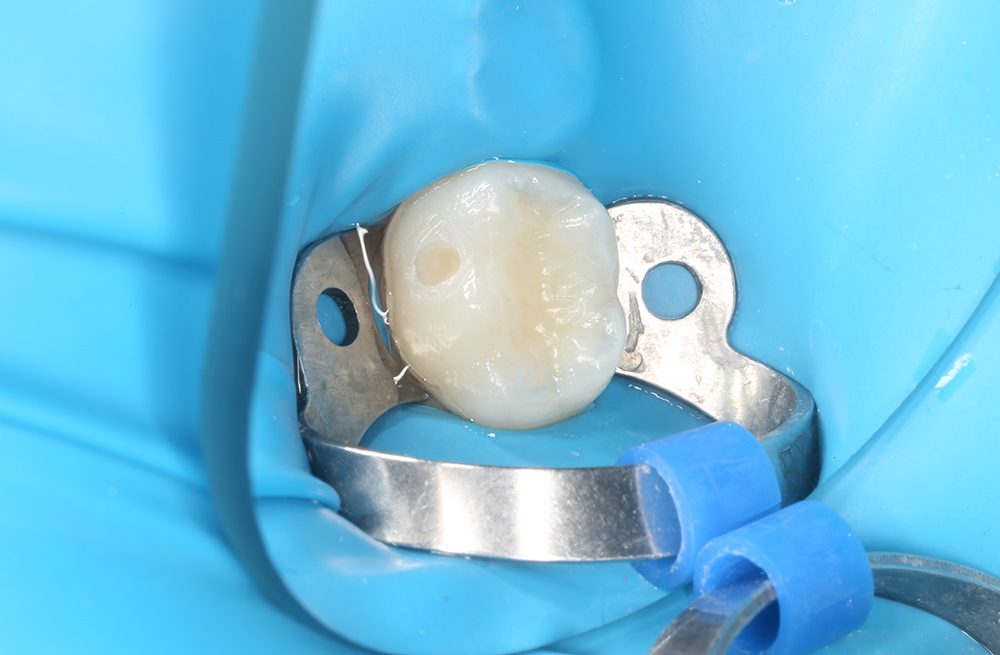

Профилактика кариеса у ребенка через герметизацию